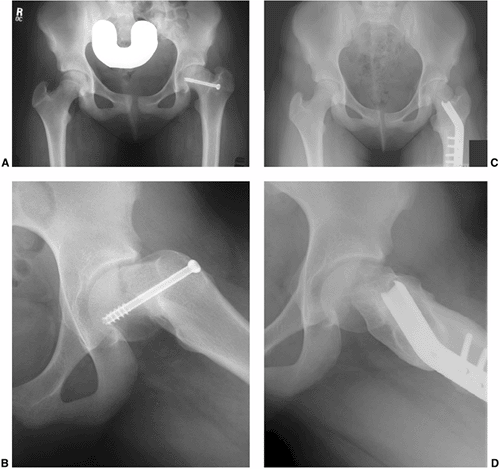

degrees of slip. With increased magnitude of slipping, the SCFE becomes

lateral border of the femoral neck) (108) (Fig. 26.1 A,B).

A SCFE is present if the Klein’s line lies cephalad to the femoral

Figure 26.1

Radiographs of a 12-year-old boy with 3 months of hip pain show typical findings of a slipped capital femoral epiphysis (SCFE). A: Anteroposterior view demonstrates physeal widening, osteopenia, decreased epiphyseal height, increased metaphyseal-teardrop distance, and asymmetry of Klein’s line. B: Although many of these features are seen on the anteroposterior view, the most striking feature is how much more easily the displacement is seen on the frog lateral view. The importance of obtaining lateral views when evaluating for SCFE cannot be overemphasized. |